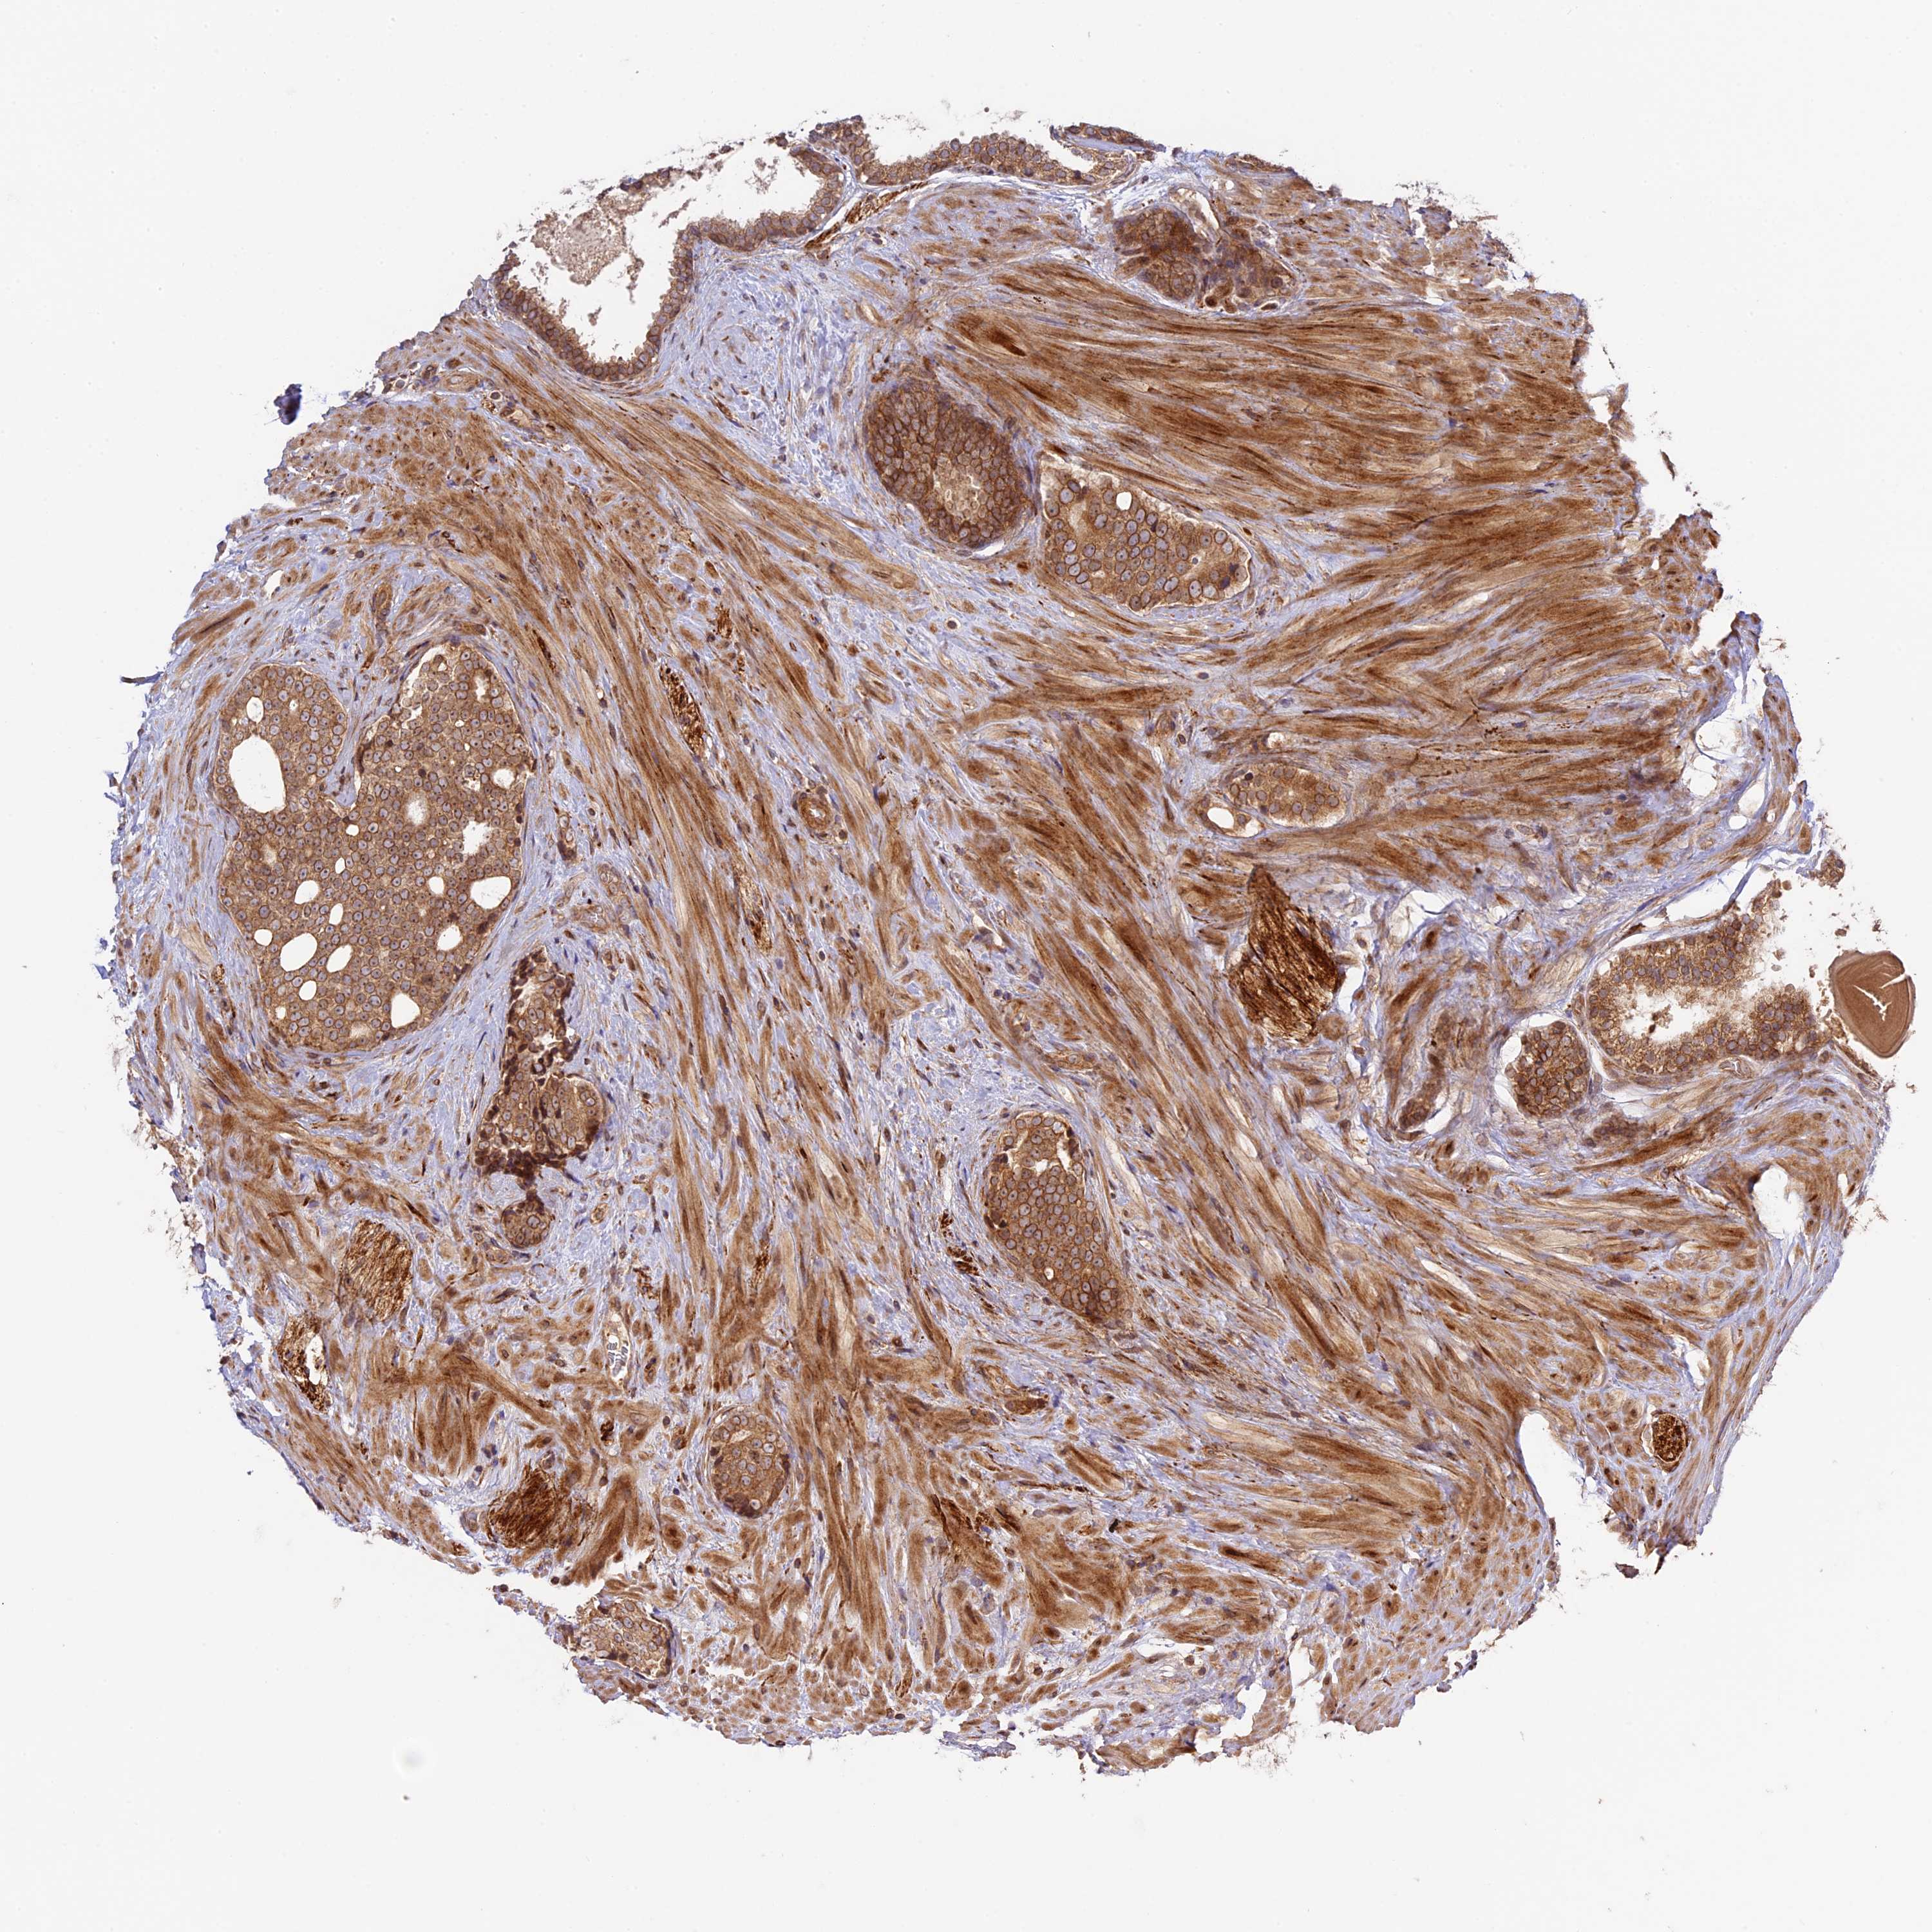

PROSTATE CANCER - Protein expressioni

A mouse-over function shows sample information and annotation data. Click on an image to view it in a full screen mode. Samples can be filtered based on level of antibody staining by selecting one or several of the following categories: high, medium, low and not detected. The assay and annotation is described here.

Antibody stainingi

Antibody staining in the annotated cell types in the current human tissue is reported as not detected, low, medium, or high, based on conventional immunohistochemistry profiling in selected tissues. This score is based on the combination of the staining intensity and fraction of stained cells.

Each image is clickable and will lead to virtual microscopy that enables deeper exploration of all samples and also displays staining intensity scores, fraction scores and subcellular localization as well as patient and tissue information for each sample.

Antibody HPA039533

Antibody HPA040355

Staining

High

Medium

Low

Not detected

Intensity

Strong

Moderate

Weak

Negative

Quantity

>75%

75%-25%

<25%

None

Location

Nuclear

Cytoplasmic/membranous

Cytoplasmic/membranous,nuclear

Adenocarcinoma, High grade

Adenocarcinoma, Low grade